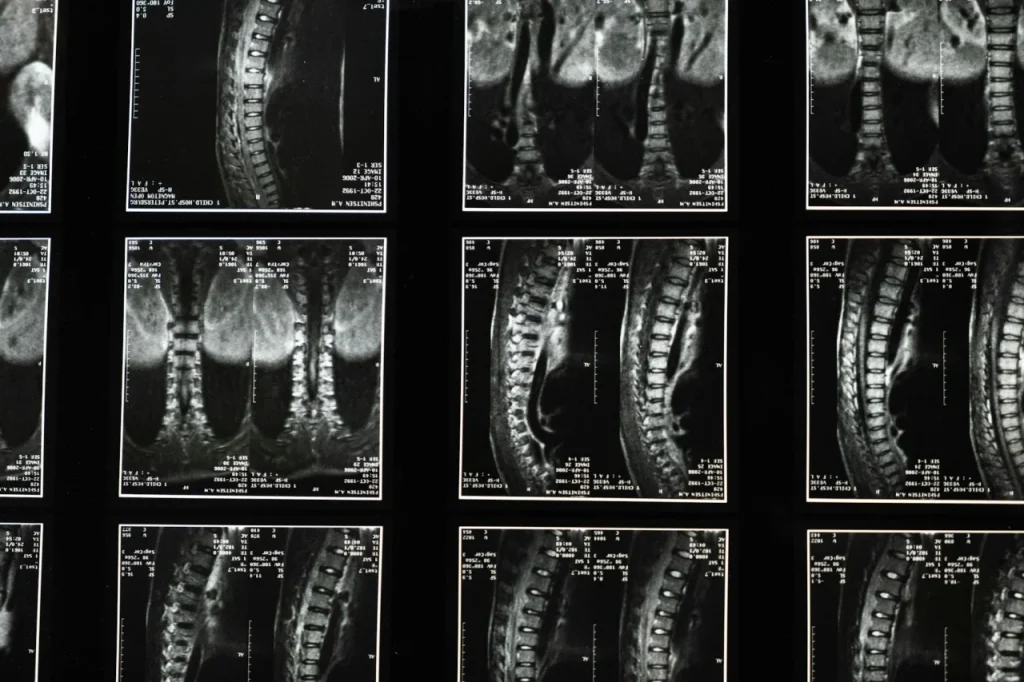

Modelos experimentais, amostras e protocolos

Foram utilizados modelos murinos e roedores maiores, com lesão medular contusiva padronizada e grupos randomizados e cegos. As amostras incluíram coortes suficientes para análise estatística, com replicações independentes e power calculado previamente. O protocolo de aplicação local da polilaminina variou concentrações e vetores de entrega, com avaliações em T0, T7, T28 e T90 dias, abrangendo análises comportamentais, eletrofisiológicas e imuno-histoquímicas, Dra. Tatiana Sampaio e Polilaminina: Entenda o estudo da UFRJ para paralisia. Foram adotados critérios rigorosos de inclusão e exclusão para reduzir viés.

Resultados principais e análise dos dados

Os resultados mostraram aumento significativo na extensão axonal e recuperação parcial de função motora nos grupos tratados, com diferença estatisticamente significativa nos escores comportamentais e nos testes de condução nervosa. A polilaminina também reduziu marcadores de gliose e inflamação local, sugerindo um microambiente mais permissivo à reparação. A análise incluiu testes paramétricos e não paramétricos, correções para múltiplas comparações e estimativas de tamanho de efeito, Dra. Tatiana Sampaio e Polilaminina: Entenda o estudo da UFRJ para paralisia. Limitações mencionadas abarcaram janela terapêutica e translação para humanos, com necessidade de estudos complementares, Dra. Tatiana Sampaio e Polilaminina: Entenda o estudo da UFRJ para paralisia.